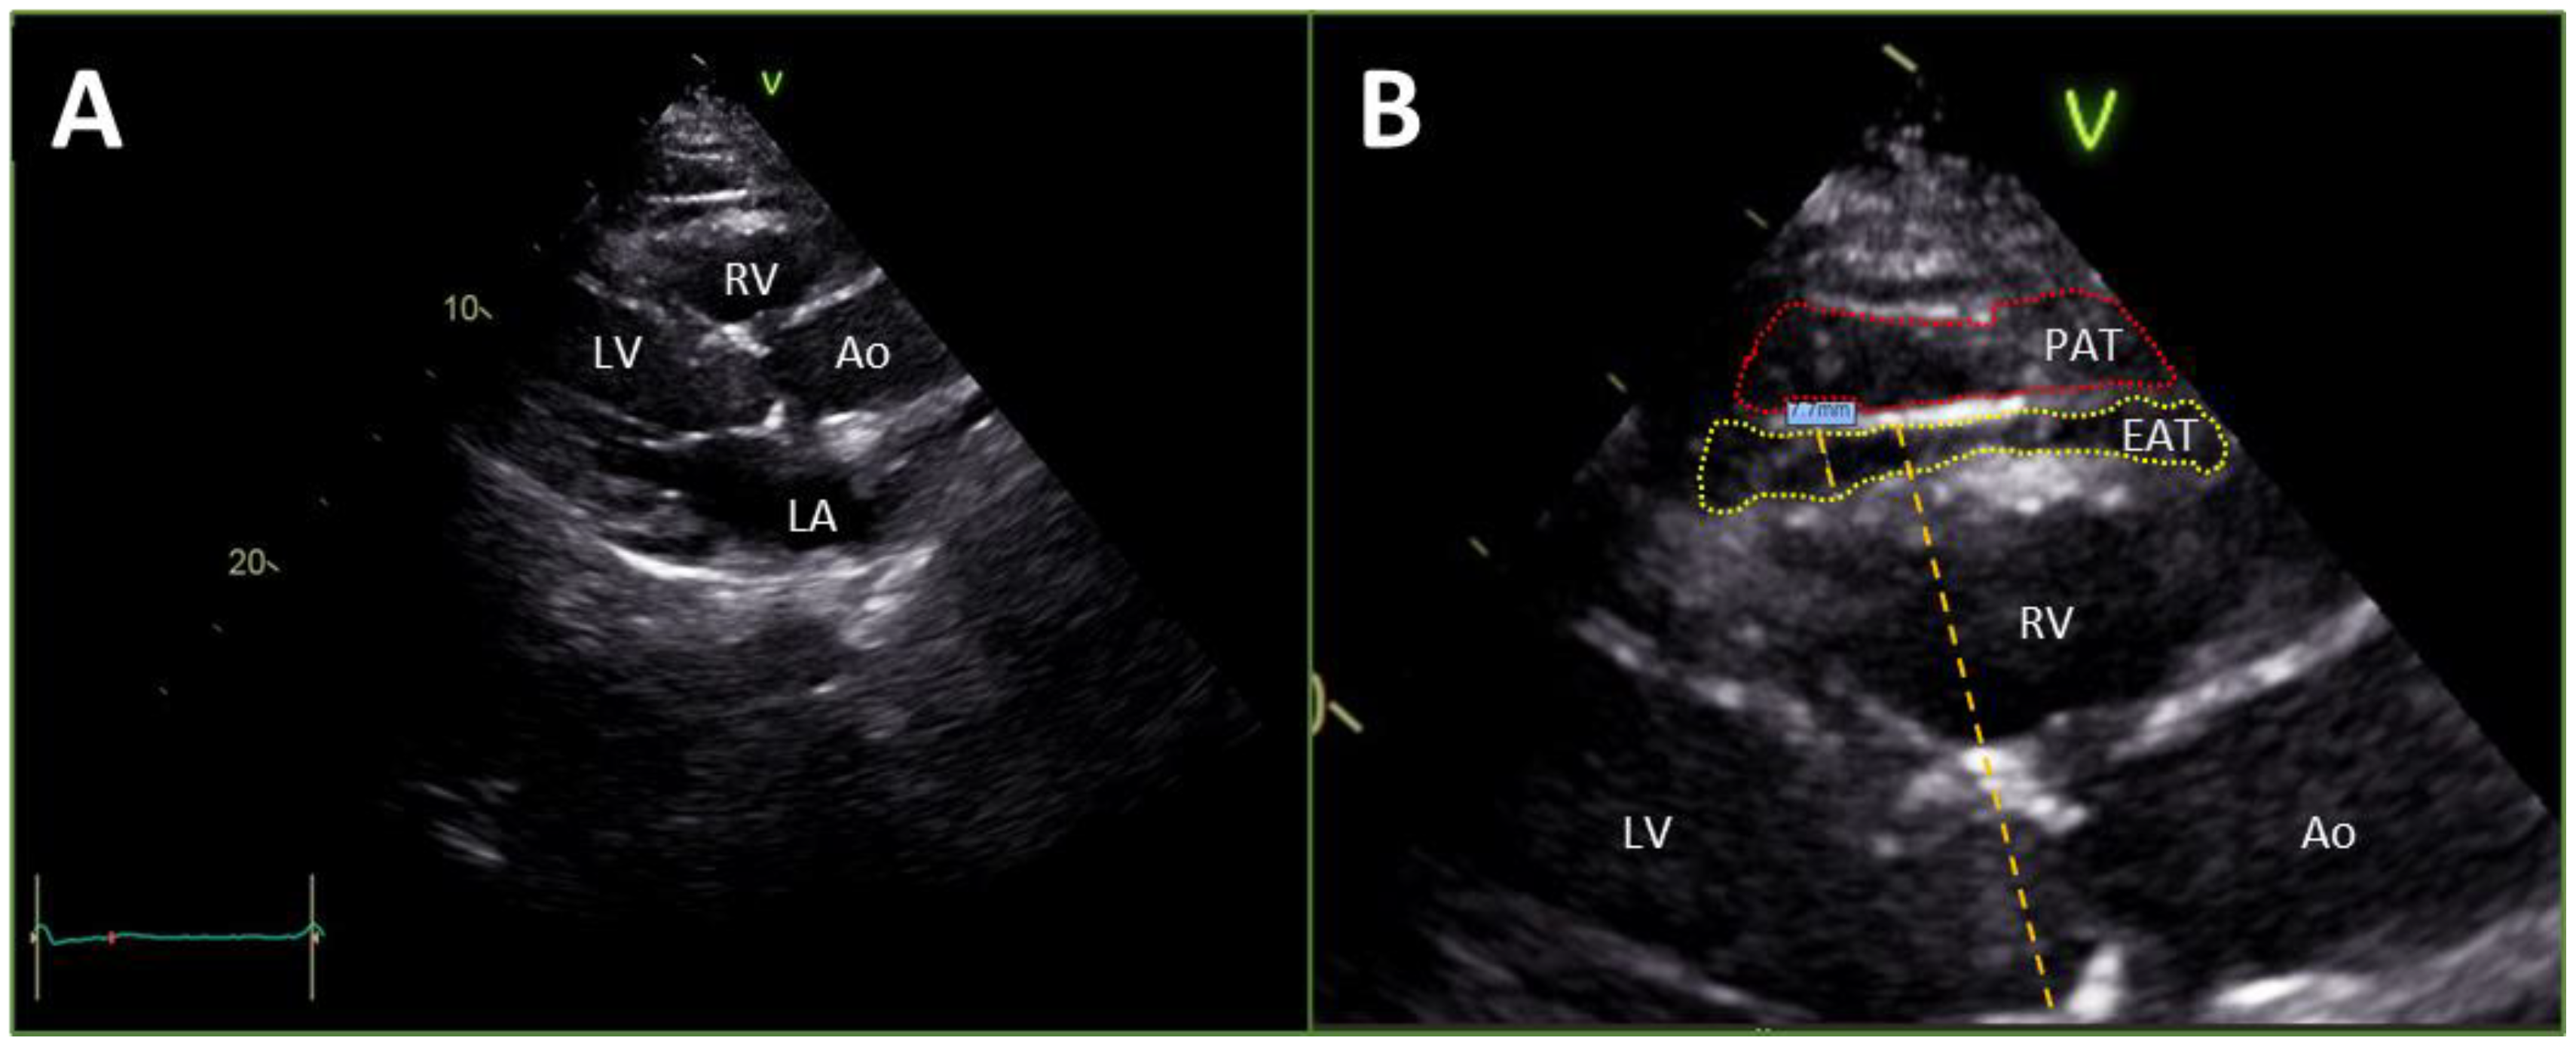

Epicardial fat thickness measurements were made from the 2D parasternal long-axis view of the transthoracic echocardiograms, perpendicular to the free wall of the right ventricle using the aortic annulus as an anatomic landmark for orientation and alignment as shown in Figure 1A,B [25,26]. To appreciate a consistent anatomical location for the purpose of measurement, epicardial fat was defined as a layer of echo-free tissue bordered by the myocardium below and visceral pericardium above [26]. Using the integrated ruler tool, the maximum epicardial fat thickness was measured at end-systole during the T wave. This approach for evaluating epicardial fat thickness has been validated against other methods of assessment of epicardial fat mass [27]. Three separate measurements were taken from three distinct cardiac cycles for each study patient and the mean value for epicardial fat thickness was computed and utilized for subsequent data analysis [25,26]. Echocardiographic measurements were made following standard procedures.

Figure 1.

(A) The parasternal long axis view from a transthoracic echocardiogram of the heart at end-systole. Depth is quantified on the right axis in centimeters. (B) [An enlargement of image in A]The measurement of EAT thickness taken perpendicular to the free wall of the RV using the aortic annulus as an anatomical landmark for alignment and orientation (as shown with the orange dashed line). EAT is circumscribed with a yellow dashed line and PAT is circumscribed with a red dashed line. Ao, Aorta; EAT, epicardial adipose tissue; LA, left atrium; LV, left ventricle; PAT, pericardial adipose tissue; RV, right ventricle.